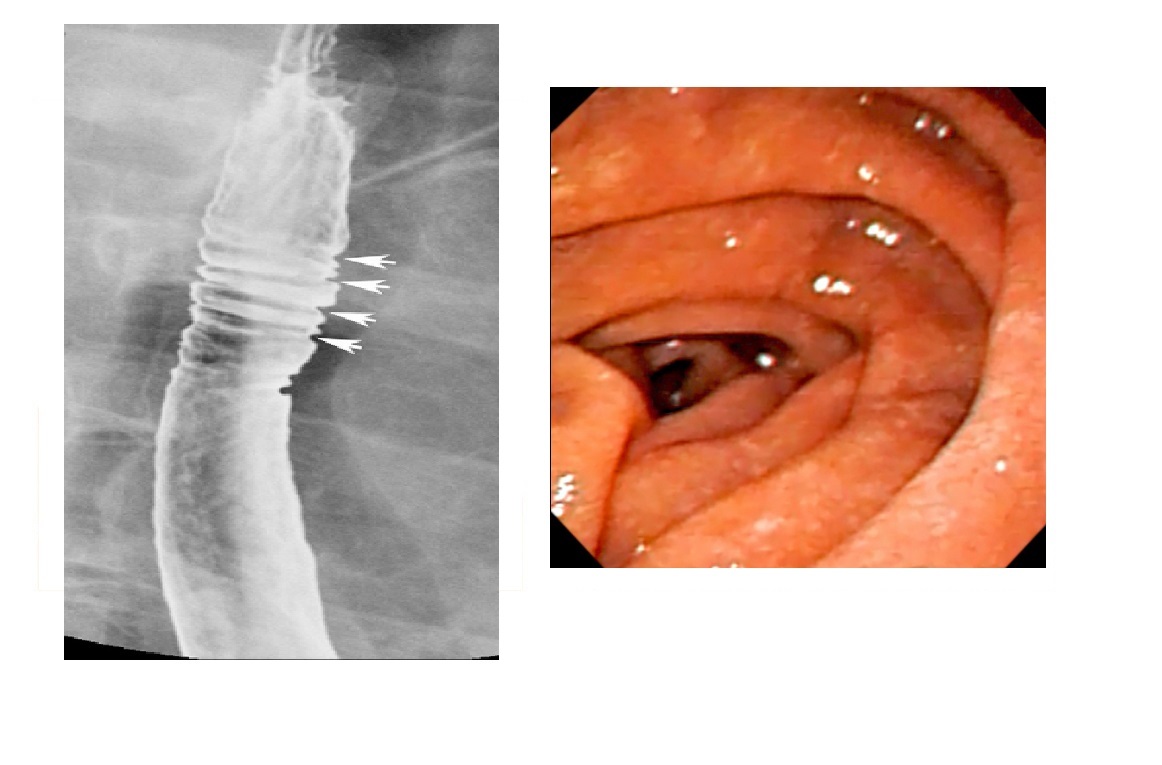

Eosinophilic oesophagitis

Barium - Concentric, ring-like strictures of oesophagus

**Not transient - Permanent **

DDx

feline oesophagus

- folds1-2 mm thick and run horizontally around the entire circumference of the esophageal lumen.

- The findings are transient, seen following reflux and not during swallowing.

- Associated with GORD

- distal two-thirds of the thoracic esophagus